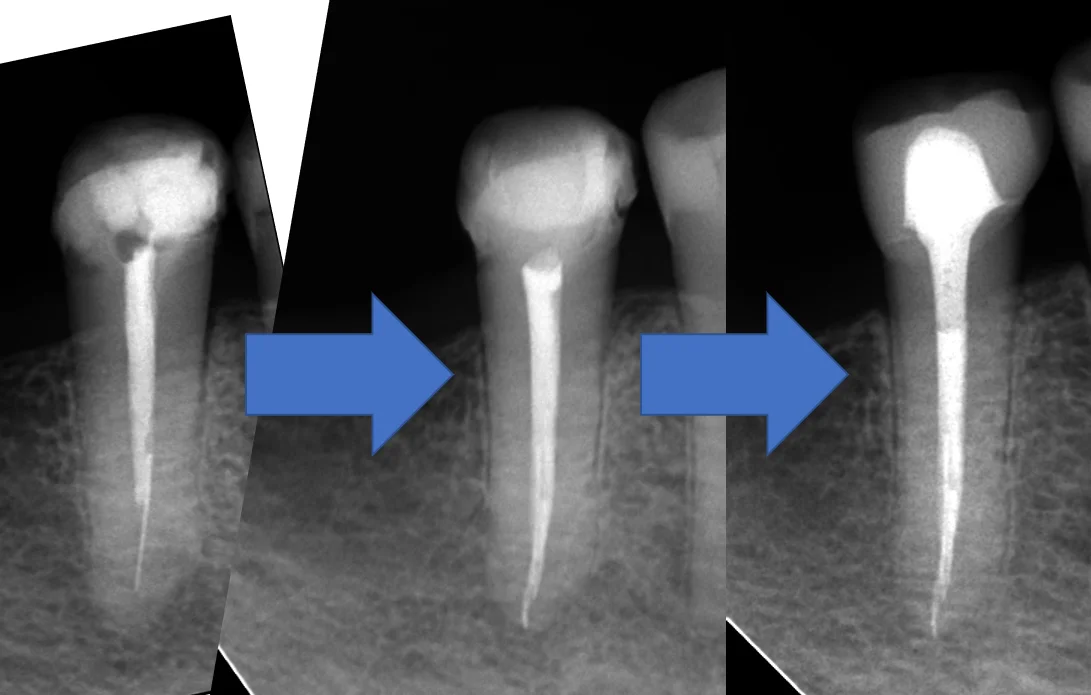

ふと定期検診で来院された日がちょうど根管充填から2年経過したタイミングだったため、折角なので、経過のレントゲンを撮らせて頂きました。

それがこちらです。

根の先には骨がしっかりと出来てくれています。(青い丸の部分)

膿があった影も完全に消失することが出来ましたね。

また入れていたセラミックの適合も非常に良好です。(紫の丸の部分)

段差も一切なく、非常に適合良く入っているのが分かるかと思います。

術前からの比較がこちらです。

分かりやすい様に角度を変えているんですが、若干トリミングに難があるのは許してください。

こうやって比較でみると根の先の膿があった所が消失しているのが分かりやすいかと思います。